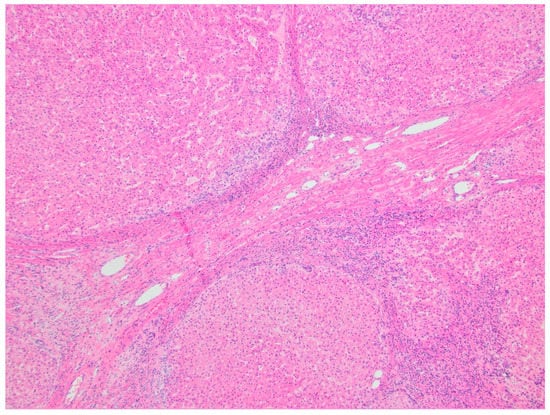

5.2.5. Histopathology and Immunohistochemistry